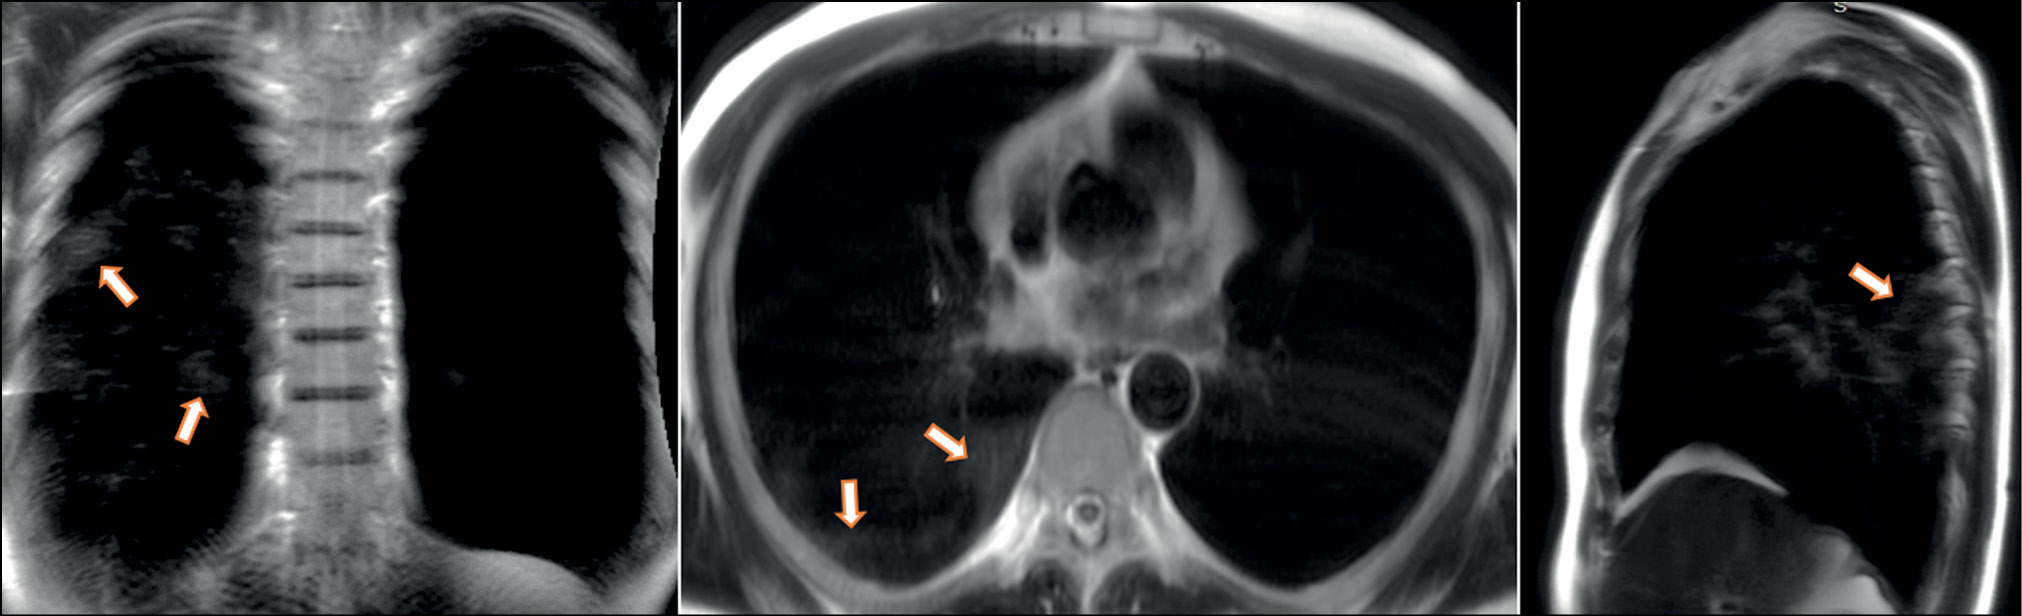

A patient (female, 25 years old) complained of a dry cough, high fever (up to 39°С), chills, and chest heaviness. She went to the hospital on the sixth day after the onset of the first symptoms, when they became extremely pronounced. Dynamic MRI showed a large area of increased signal in segments S6, S8, and S9 of the left lung’s lower lobe. An inhomogeneous increased signal was found during inhalation in the coronal, axial, and sagittal planes (Fig. 3). The signal intensity increased in the coronal and sagittal planes during exhalation (Fig. 4), with the increased visual size of the affected areas and the expanded “cloudy sky” area. These findings may be attributed to expiratory contraction of lung tissue during exhalation.

Figure 4. Dynamic magnetic resonance imaging of the lungs during exhalation in the coronal, axial, and sagittal planes. Arrows point to lesions with areas of both marked interstitial changes (the sign of the “cloudy sky”) and alveolar (compaction) changes that can be differentiated during inhalation (see Figure 3).

Chest breathing movements can also influence scanning and thus the observed pattern. The “cloudy sky” observed at the periphery of the signal enhancement area during inhalation becomes more intense during exhalation, most likely due to increasing density of the lung parenchyma.